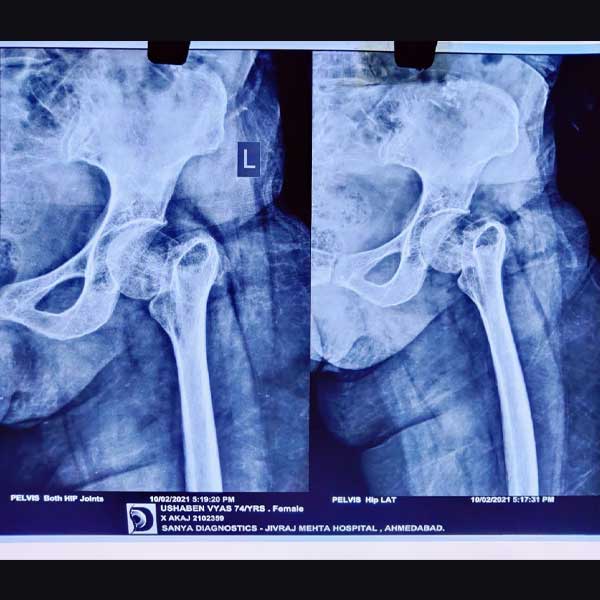

Case 1 - Hip Hemiarthroplasty

A female patient, aged 72 years. She had been diagnosed to have a Closed fracture of neck Fracture. She was treated operatively with Hip Hemiarthroplasty.

Pre-Operative